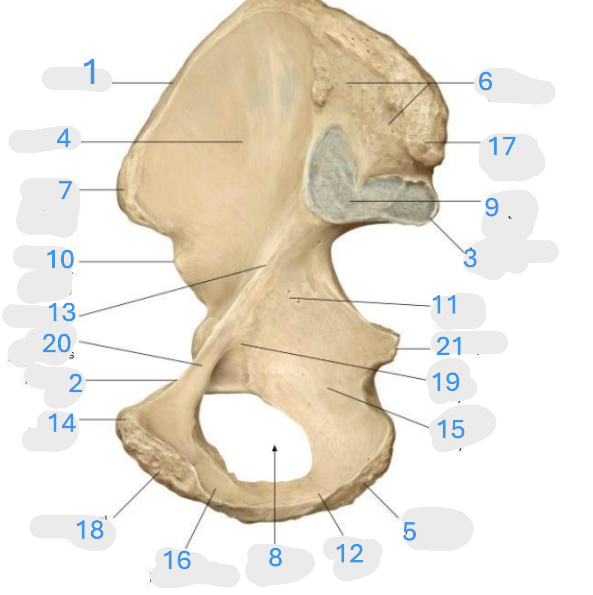

Where is the iliac crest

1

where is the sacral canal

2

Where is the iliac tubercle

3

Where is the outer lip

4

Where is the inner lip

5

Where is the iliac fossa

6

Where is the pectineal line (pecten pubis)

7

Where is the sacroiliac joint

8

Where is the ischial spine

9

Where is the iliac tuberosity

10

Where is the promontory

11

Where is the arcuate line

12

Where is the anterior superior and inferior iliac spine

13

Where is the intermediate line

14

Where is the ala of the sacrum

15

Where is the coccyx

16

Where is the pubic crest

17

Where is the pubic tubercle

18